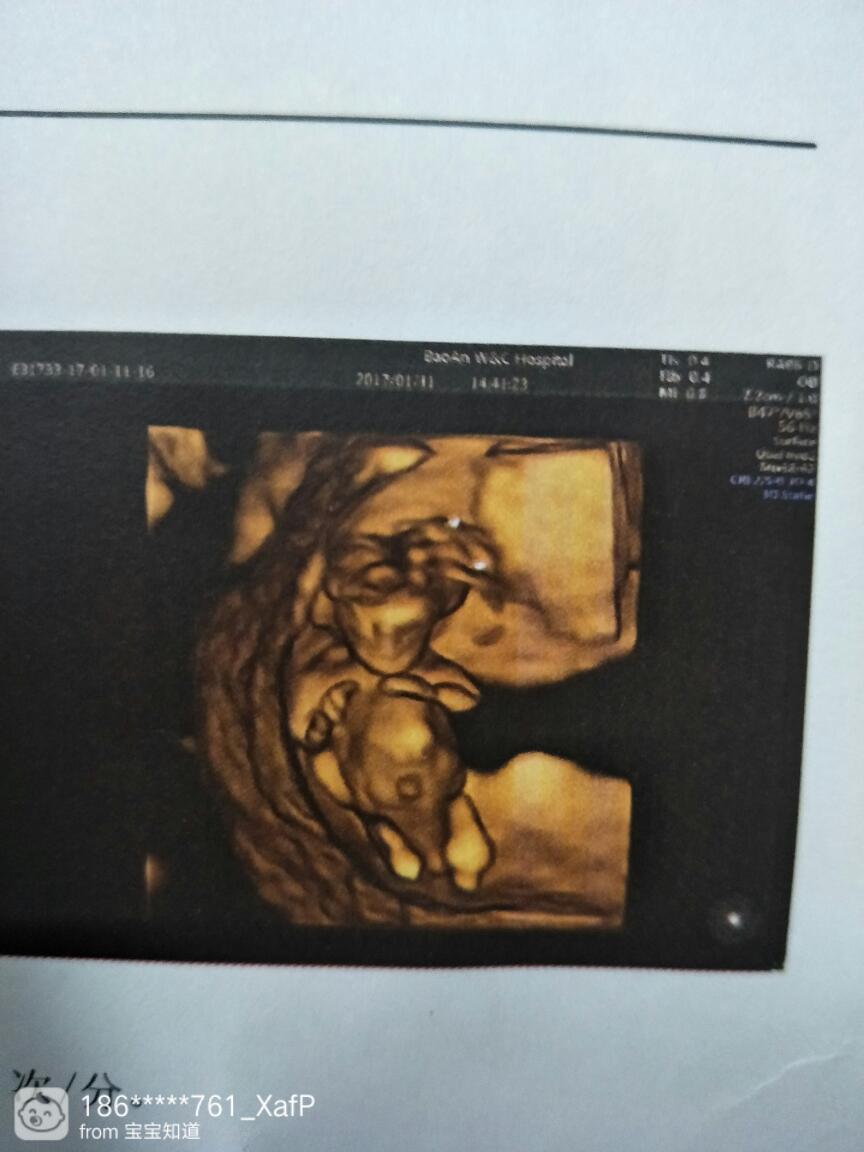

为什么二胎也是这样?真的畸形?

2014年5月意外,有了,14周照b超发现有问题,不能留着,还为是环境各方面的问题。可2016年10月,也是意外,再次怀孕,前天做B超检查,担心的事还是发生导耗了!这个孩子到底是畸形了?还是发育貌抓不全?看着这B超图,感觉他好像在微笑,小小的生命,真的就要这样结束了吗?到底是什么原因?都没有什么病挤近清呀!也没乱吃东西啊!